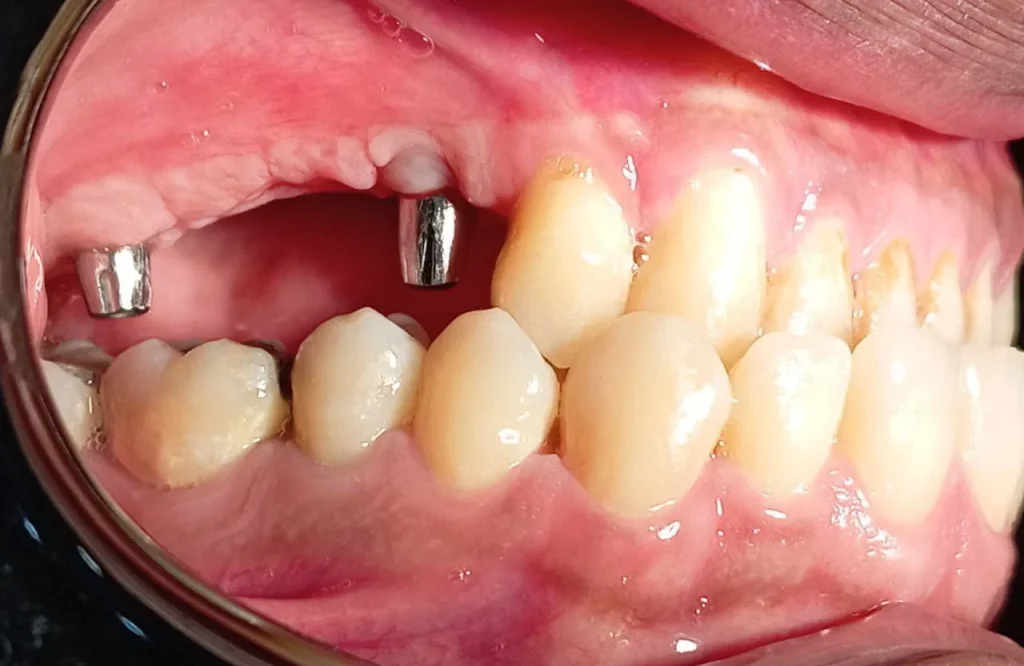

پاکت به فرو رفتگی بین دندان و لثه گفته می شود. در التهاب یا عفونت لثه این شیار عمیق تر شده و فضای مناسبی برای میکروبها فراهم می کند. در این عمل، جراح لثه را برش میزند و به بالا تا میزند تا باکتریها و آلودگی های زیر آن را تمیز کند. سپس بافت لثه به دور دندان بخیه می شود تا دوباره رشد کرده و دندان را احاطه کند.

در این نوع جراحی، برشی در لثه ایجاد می شود و بافت برش خورده کنار زده می شود تا باکتریها و آلودگی ها برداشته شوند. سپس پیوند استخوان، غشا یا پروتئینهای تحریک کننده تولید بافت (و یا ترکیبی از هر سه) در این محل جایگذاری می شود تا بافت لثه بازسازی شود.